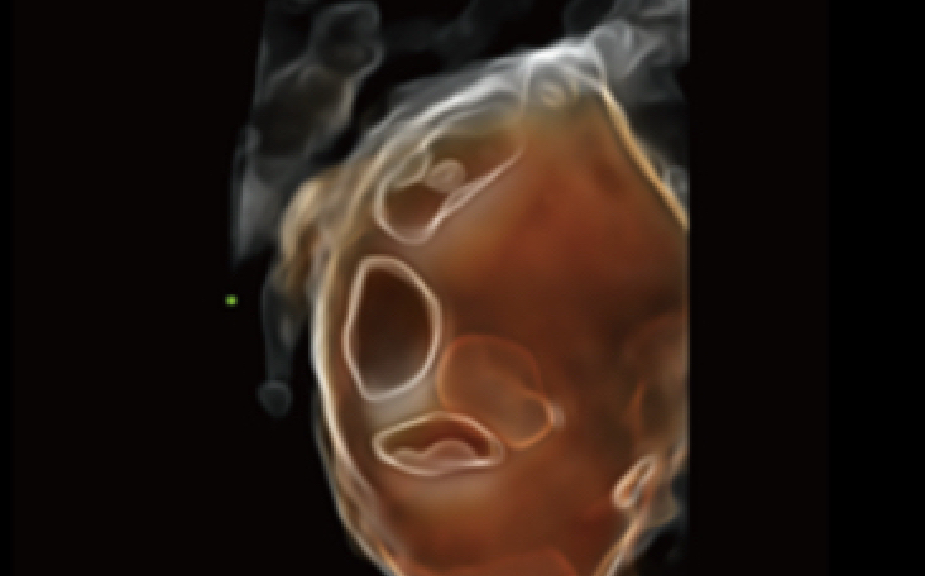

Dandy Walker y ACC

Smart Planes CNS MRI

CM anormal con sospecha de síndrome de Dandy Walker

Tecnología pionera exclusiva de Mindray que permite la detección completamente automática y precisa de los planos más significativos y las mediciones más frecuentes del SNC del feto, lo que conduce a un diagnóstico inteligente, un mejor rendimiento y una menor dependencia del usuario. Smart Planes CNS es una herramienta fácil de usar que mejora significativamente la eficiencia de la exploración gracias a su mayor precisión y a su operación automática. Con tan solo hacer clic en un botón sobre una imagen del volumen cerebral fetal en 3D, se generan, de manera inmediata, los planos de exploración del SNC estándares (MSP, TCP, TTP y TVP) y un conjunto de mediciones anatómicas relacionadas (BPD, HC, OFD, TCD, CM y LVW).